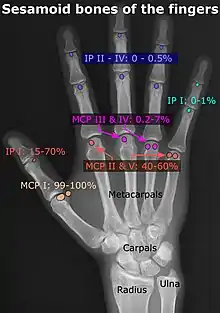

- In the hand—two sesamoid bones are commonly found in the distal portions of the first metacarpal bone (within the tendons of adductor pollicis and flexor pollicis brevis). There is also commonly a sesamoid bone in distal portions of the second metacarpal bone and fifth metacarpal bone.[7]